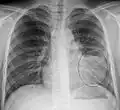

Normal AP CXR

Normal lateral CXR -